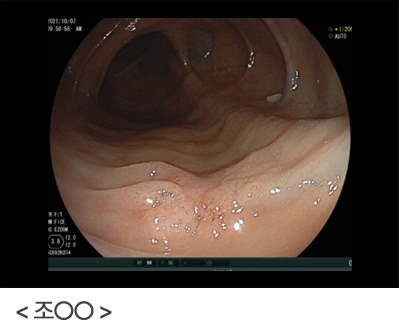

단 한 번의 내시경 검사로, 위암을 진단 못할 수도 있습니다. 위통이나 속 쓰림, 소화불량 등의 증상이 있고 위암일 가능성이 조금이라도 있다면 다시 위내시경을 시행하여 확인하는 것이 중요합니다. 위내시경 시행 후 괜찮다고 안심하지 마시고, 증상이 지속되거나, 위암의 고위험군이라면 지속적인 위내시경 검사를 하시는 것이 좋습니다.